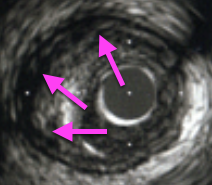

不安定プラークのIVUS画像はプラーク部分に黒く抜けた影があるのが特徴だ!

不安定プラークは

プラーク内部にやわらかい脂質が貯まっている病変だぞ!

不用意に拡張すると、にきびを潰したようにビュッと脂質が外に飛び出し、

飛び出した脂質が末梢の血管を閉塞させるリスクがある。

そのため、フィルトラップやパラシュートといった末梢保護デバイスの使用を検討し、

万が一、プラーク内の脂質が末梢に飛んでいった時に備えるんだ。

また、不安定プラークは柔らかいため、

バルーンで拡張するとプラークがムニュっと横移動することがある。

*この横移動をプラークシフトといいます。